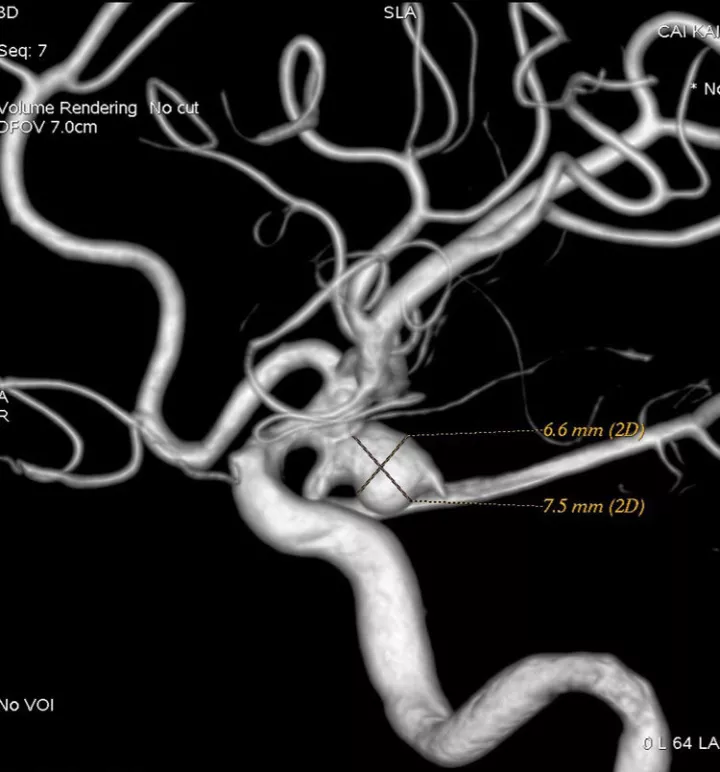

我们来看看动脉瘤的结构:红色为颈内动脉走向,绿色为后交通动脉走向,蓝色为动脉瘤

栓塞的要点,既要致密填塞,又要保证颈内动脉和后交通动脉的通畅。决定通过对侧前交通动脉-颈内动脉远端-后交通动脉途径来置入输送支架的微导管,从后交通动脉释放支架直到颈内动脉末端,以达到一个支架对颈内动脉和后交通动脉的保护